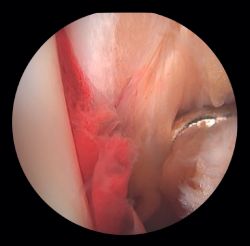

La artroscopia asiste a la RAFI para evaluar la congruencia de la superficie articular. Es especialmente útil para la reducción del maléolo medial. La tasa de mal reducción en fracturas del maléolo medial es del 22,2 al 32,6%(15,16). La artroscopia inicial permite valorar si la reducción del maléolo tibial puede realizarse de forma abierta o cerrada. En casos con desplazamiento significativo, se opta por una síntesis abierta, manteniendo siempre control artroscópico durante el procedimiento para asegurar una reducción precisa y evitar la rotación del fragmento distal (Figura 4).

Los pacientes con mayor riesgo de mala reducción son pacientes mayores de 60 años por la calidad ósea disminuida y fracturas más complejas(17). Los pacientes con fracturas abiertas y fracturas luxaciones presentan un riesgo 2,15 a 2,7 veces mayor, respectivamente, debido al mayor daño de los tejidos blandos y la complejidad de la fractura. Las fracturas verticales y con tejidos blandos interpuestos dificultan lograr una reducción anatómica(15,16).

Si la lesión del deltoideo compromete solo a la parte anterior, podremos realizar la reinserción de forma artroscópica mediante implantes reabsorbibles. Si la desinserción del deltoideo es completa, preferimos realizar la reinserción de forma abierta por la dificultad que entraña colocar los implantes en la zona posterior del maléolo y el riesgo de lesión neurovascular (Figura 5).